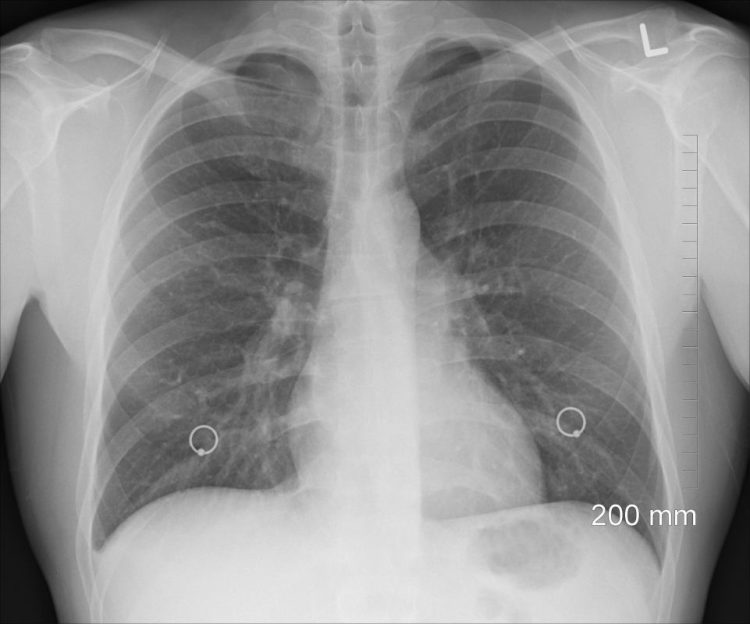

Il tumore del polmone è il big killer tra tutte le malattie oncologiche, causando ogni anno la morte di 34.000 persone in Italia, con numeri sempre più in aumento. Esistono due principali tipi di tumore del polmone, che rappresentano oltre il 95% delle diagnosi, i quali si dividono a loro volta in numerosi ulteriori sottotipi determinati da mutazioni genetiche.

Grazie ai continui progressi della ricerca scientifica, lo scenario terapeutico del tumore al polmone non a piccole cellule (NSCLC) sta evolvendo rapidamente, permettendo di avere trattamenti sempre più mirati, anche per pazienti che presentano mutazioni rare, come ad esempio quelli le inserzioni dell’esone 20 del fattore di crescita dell’epidermide (EGFR), in grado di aumentare l’aspettativa e la qualità di vita delle persone con questa malattia.